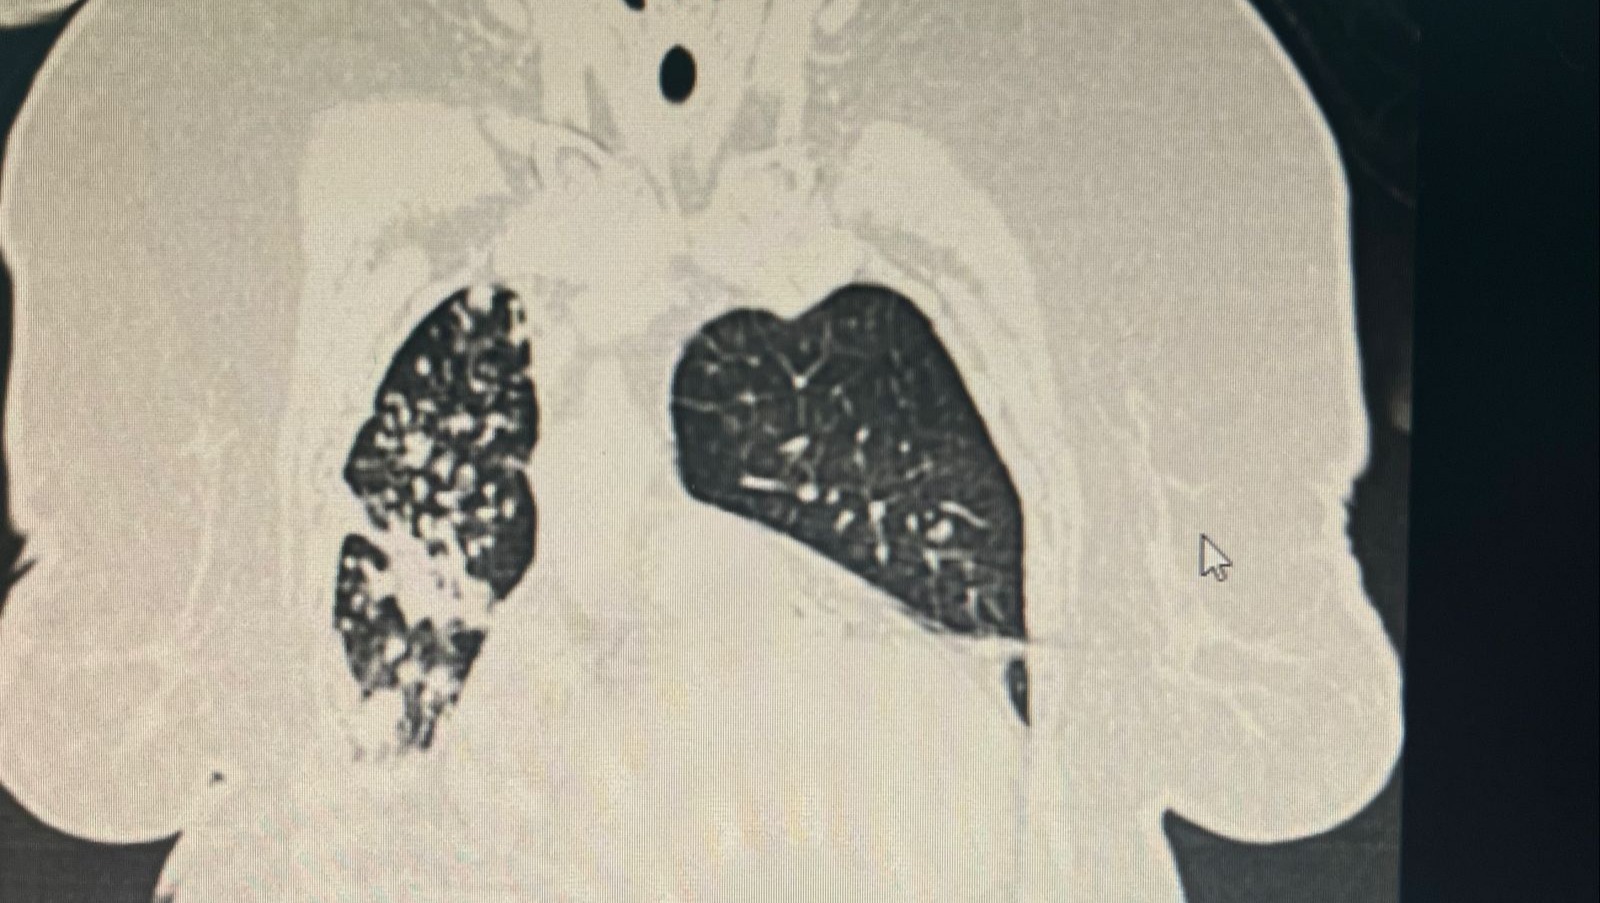

My mother Delfa Pernía underwent catheterization due to two heart attacks, she has also been connected to oxygen because she has a chronic lung infection and at the moment is in a critical state of decompensation for which she was admitted to the intensive care unit (ICU) in San Cristóbal Venezuela, due to the health conditions she needs to be in said care to ensure her health for at least 15 days, the situation is made worse by the country's situation and the conditions of the hospitals that do not have the necessary supplies; each day in the intensive care room it costs $ 700 per day to keep her intubated, to this must be added the additional cost of the doctors, the necessary treatments, and the cost of each study that is done.

Mi madre Delfa Pernía fue sometida a Cateterismo a causa de dos ataques al corazón, también ha estado conectada a oxígeno ya que tiene una infección crónica en los pulmones y en el momento se encuentra en un estado de descompensación crítico por lo que fue ingresada a la unidad de cuidados intensivos (UCI )en San Cristóbal Venezuela, debido a las condiciones de salud ella necesita estar en dicho cuidado para velar por su salud por mínimo 15 días , la situación se empeora más por la situación país y las condiciones de los hospitales que no cuentan con insumos necesarios; cada día en la sala de cuidados intensivos cuesta para mantenerla entubada 700 $ por día, a esto hay que sumarle el costo adicional de los doctores , los tratamientos necesarios, y el costo de cada estudio que se le hace.